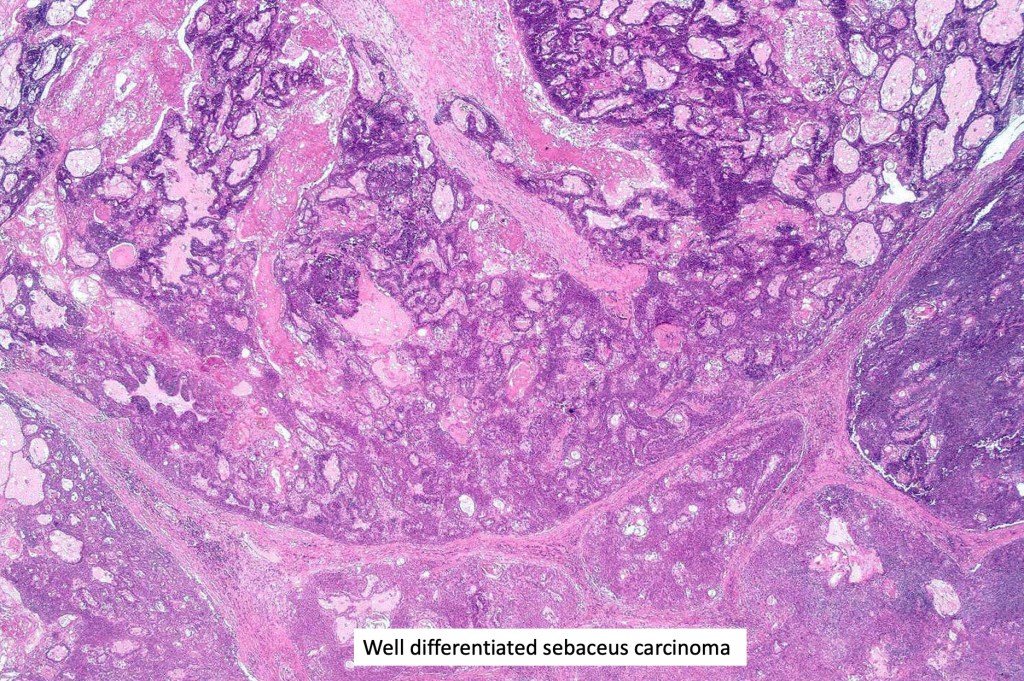

•Well differentiated lobular growth pattern though to a poorly differentiated tumor often showing a diffuse, infiltrating border which may extend into the subcutaneous fat

•Well differentiated examples can be deceptive unless one looks carefully for pleomorphism, necrosis, excessive mitotic activity and abnormal mitoses. Be careful diagnosing sebaceous adenoma, particularly large examples arising in the elderly

•May be graded into well, moderate & poorly differentiated categories. I am not sure that this has any great value

Sebaceous carcinoma from a patient with Muir-Torre syndrome kindly shared by Dr. Antonina Kalmykova.